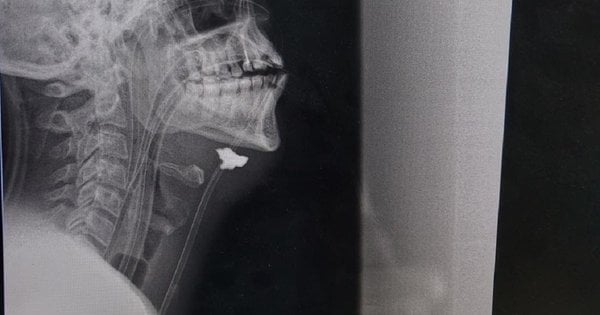

„След прегледите на пациента е поставена диагноза огнестрелна и шрапнелна сляпа рана. Фрагментът е открит в проекцията на съдов сноп, хематом и признаци на нараняване на сънната артерия вдясно. С други думи, фрагмент от снаряда е ударил рамото, преминал е през целия врат, разкъсал е сънната артерия и е спрял под челюстта“, разказва ни Тарас Кобза, съдов хирург, който от дълго време спасява войници в източната част на страната.

Защитникът е откаран в болница на първа линия в критично състояние, натискът вече не е определен. Той претърпя реанимация и след стабилизиране на състоянието му беше извършен спешен преглед: рентгенова снимка на главата, шията и гръдния кош, ултразвук на каротидните артерии.